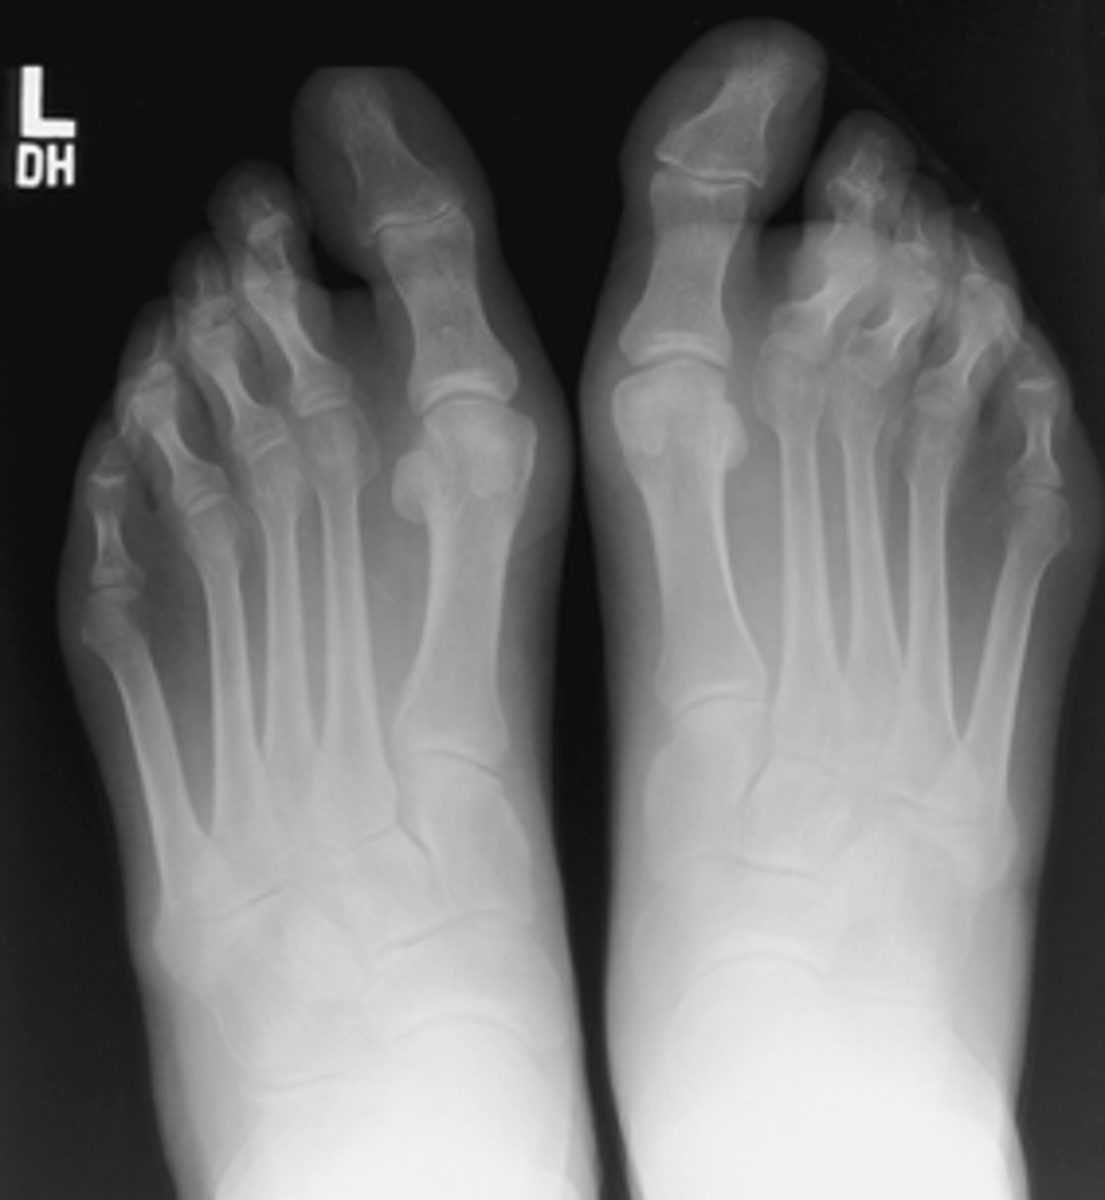

AP Weight Bearing Foot

What projection is this?

Evaluation Criteria for AP Weight Bearing Foot

- CR 15 posterior

- CR to base of MTs

- Bilateral feet demonstated

- Phalanges and MTs not rotated